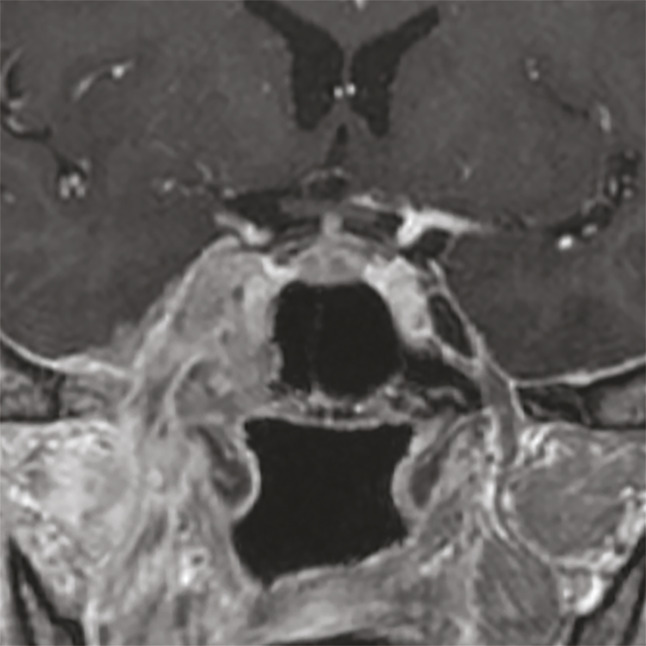

Pour le bilan initial, il est recommandé d’effectuer une IRM cervico-faciale explorant l’axe pharyngé, les espaces profonds de part et d’autre de la base du crâne pour ne pas méconnaître les extensions périnerveuses, et les aires ganglionnaires (fig. 1). En cas de non-disponibilité ou de contre-indication à l’IRM, une TDM cervico-faciale avec injection biphasique de produit de contraste peut être réalisée. Un scanner de la base du crâne permet de rechercher une lyse corticale si l’IRM montre un contact ou une infiltration médullaire osseuse. Une tomographie par émission de positons-tomodensitométrie (TEP-TDM) est réalisée pour rechercher des localisations ganglionnaires et secondaires dans les stades avancés. L’ensemble de ces éléments permet d’établir la classification clinique TNM.2

En TDM, au cours de l’acquisition en respiration douce, les sinus piriformes sont souvent fermés, et les trois parois (antérieure, latérale et postérieure) ne sont pas analysables de façon satisfaisante. Il est donc nécessaire de compléter l’examen par une hélice au cours de laquelle le patient réalise une manœuvre de Valsalva, ce qui dégage les reliefs anatomiques. La lésion apparaît développée aux dépens d’une ou plusieurs de ses parois (fig. 4), faisant plus ou moins saillie dans la lumière pharyngée, et/ou infiltrant les parties molles profondes tant latéralement que dans l’axe vertical (espaces graisseux parapharyngés, muscles laryngés, structure glottique, bouche de l’œsophage, base de la langue).